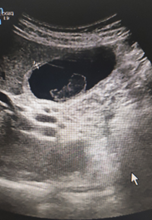

ECOGRAFIA CLÍNICA:  Se aprecia vesicular biliar bien repleccionada con imagen en su interior redondeada, hipoecoica, sin sombra, Murphy ecográfico positivo.

La clínica ya orienta el diagnostico pero la Ecografia filia el origen.

Lo llamativo para mi del caso fue visualizar un calculo biliar sin sombra (calculo blando) , saber de su caracteristicas ecograficas y tenerlo como opción diagnóstica.